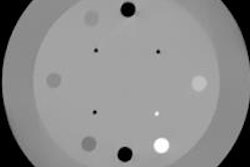

To assess their proposed approach, Pignol and colleagues obtained DECT images of a heterogeneous phantom using a commercial CT scanner. The phantom is composed of two acrylic cylinders, each containing four inserts of materials mimicking muscle (acrylic), fat (polypropylene), water (Virtual Water), and bone (Teflon).

Performing the CT scans at two energies (140 and 90 kVp) enables calculation of the attenuation and mass energy absorption coefficients needed for the ICF formulation. The ICF calculation also requires imaging of two reference materials -- cylinders of water and polyethylene in this case, which were placed by the phantom and scanned concurrently.

Isodose lines for seeds placed in all inserts. Blue, green, and red contours represent film dosimetry measurements, TG-43 and ICF-corrected TG-43 dose distributions, respectively.Finally, the researchers examined the dose distributions with seeds placed in all of the inserts -- creating a seed implant configuration of eight seeds spaced 1.5 cm apart in a cubic structure. Here, the GI passing rate improved from 40.8% to 90.5% when ICF was added to TG-43. This excellent agreement with film measurements -- attributed to smoothing effects and cross coverage of other seeds -- is particularly important because clinical implants employ multiple seeds to deliver dose.